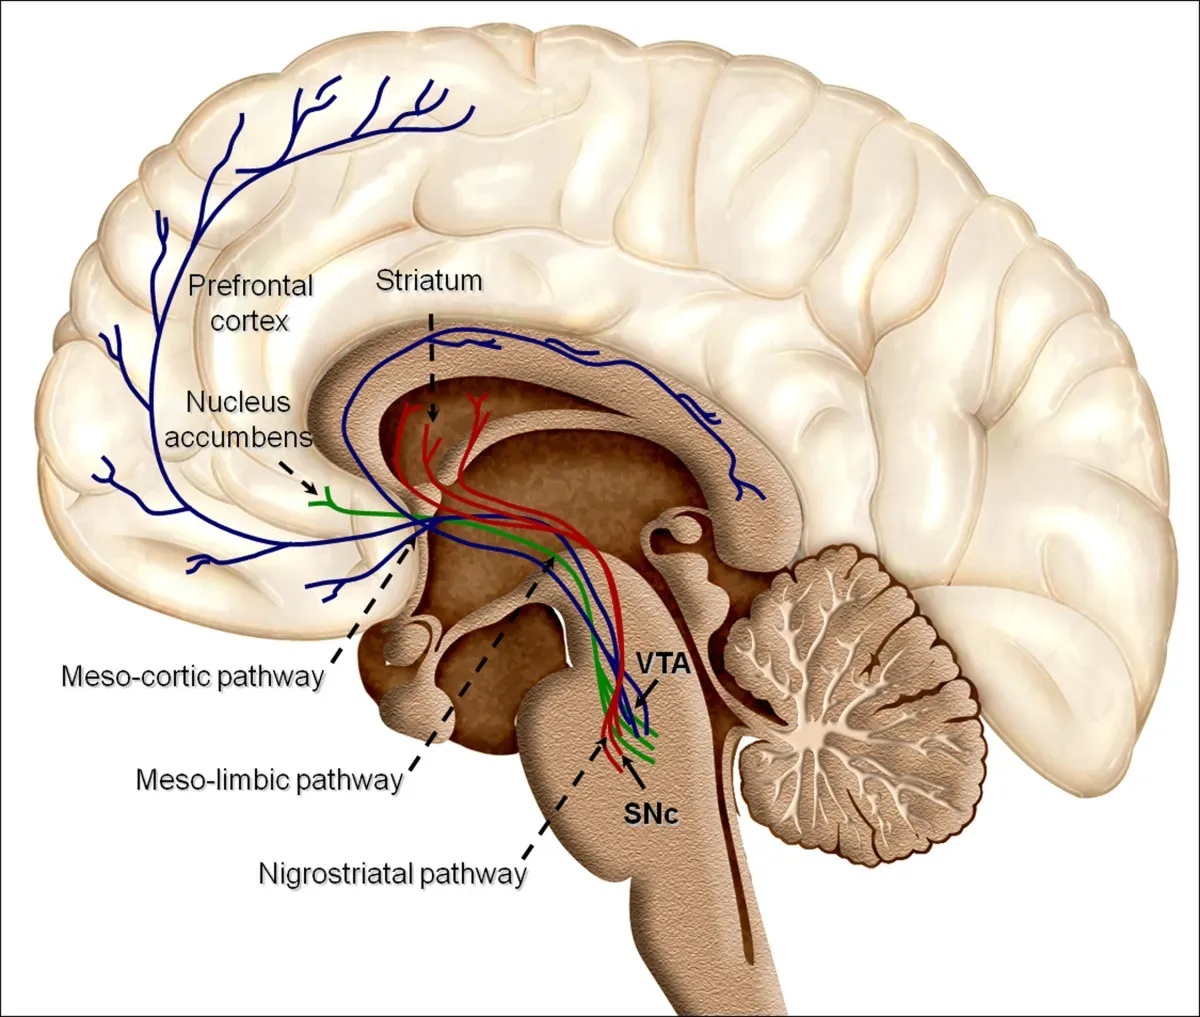

You’ve probably experienced a moment where your heart was pounding before your brain even understood what was happening. That’s not random. That’s the architecture of your emotional circuitry working exactly as designed. Emotion processing often occurs faster than conscious thought. The amygdala can detect threats milliseconds before the prefrontal cortex evaluates them, explaining instinctive reactions. Your ancient alarm system fires before your rational self can even ask, “wait, should I be scared right now?”

Emotions are not governed by a single “emotional center” in the brain. Instead, they arise from a complex network of brain regions working in harmony. Understanding what part of the brain controls emotions requires exploring several key structures, including the amygdala, prefrontal cortex, and limbic system. Think of it less like a single control room and more like a parliament of regions, constantly negotiating. The prefrontal cortex thinks relatively slowly and carefully, with conscious, labor-intensive efforts to figure things out. The amygdala reacts automatically, impulsively, and extremely fast, and its operation is mostly unconscious. The tension between these two systems is essentially the tension between reason and gut feeling – a battle you fight daily.